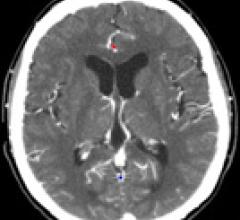

Contributing Editor Greg Freiherr offers an overview of computed tomography (CT) advances at the Radiological Society of North America (RSNA) 2015. The video includes Freiherr during his booth tours with some of the key vendors who were featuring new technology.

Technology Report:

Computed Tomography (CT)